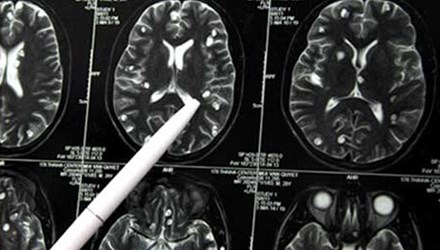

Sinh vật này là một con sán dàn tới 8cm vẫn còn sống. Các bác sĩ ở Trung Quốc đã gắp nó ra từ não của một nữ bệnh nhân. Nguyên nhân là do cô có thói quen uống nước lã trong suốt thời gian dài.

Theo Health MSN, Lý Vũ mang thai khoảng tháng thứ 3 thì bắt đầu có hiện tượng co giật. Tay chân cô thường xuyên lên cơn co giật và tê liệt. Lý Vũ đã chữa ở rất nhiều bệnh viện, cuối cùng phát hiện nguyên nhân bệnh là một con ký sinh trùng trong não.

Các bác sĩ một bệnh viện tại Quảng Đông đã phẫu thuật gắp ra con sán dài khoảng 8 cm từ não của Lý Vũ. Bác sĩ cho rằng ký sinh trùng này có thể liên quan đến thói quen uống nước lã của cô trong suốt thời gian dài.

Đến tháng 10 năm nay cô mới được các bác sĩ ở Thượng Hải chẩn đoán có ký sinh trùng trong não, uống thuốc diệt sán một thời gian nhưng không giết được con ký sinh trùng. Sau đó các bác sĩ tại Quảng Đông đã mổ não bệnh nhân gắp ra con sán còn sống. Sau phẫu thuật, sức khỏe Lý Vũ đã hồi phục và sắp được xuất viện.